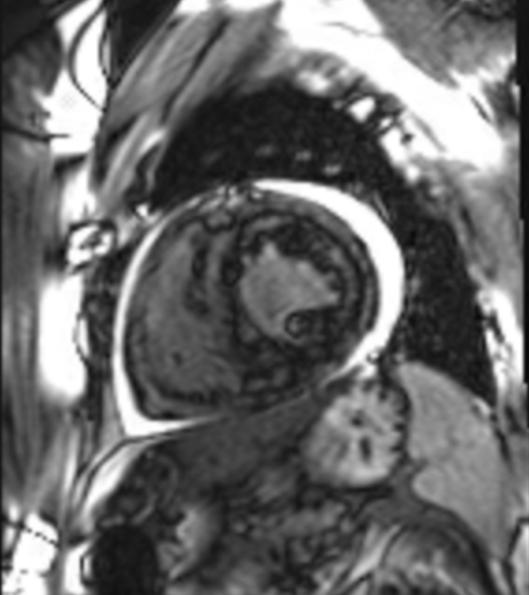

王福军主任及罗亚雄主任查房后分析患者无肥胖、肺气肿及大量心包积液等,心脏外因素所致心电信号传导受阻所致低电压可能小。而患者心肌均匀增厚,有限制表现,心肌内异常物质的浸润或贮积所致低电压可能性大,如心脏淀粉样变性、铁超负荷、溶酶体或糖原贮积等。患者心脏超声虽未见心肌内颗粒样强回声影,但淀粉样变性不能完全排除,进一步完善心脏磁共振见左室心肌存在明显的钆延迟强化。

图3.心脏磁共振心肌增厚,左室心肌明显钆延迟强化